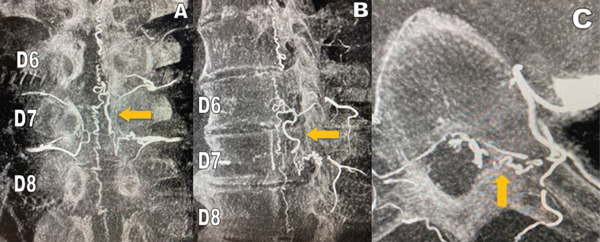

Por los antecedentes anteriormente mencionados y con el requerimiento de un centro de mayor complejidad, se decide la derivación a nuestra institución para su estudio. Al interrogatorio el paciente relata dolor lumbar y ciatalgia bilateral de más de 18 meses de evolución, con dificultades en la marcha, que progresaron hasta necesitar asistencia en silla de ruedas, agregando afectación esfinteriana en el último tiempo. Al examen físico, presentó paraparesia flácida severa, hiporreflexia tendinosa y nivel sensitivo desde T10. Se interpretó en un primer momento, por imágenes previas, como Mielomalacia en estudio. Por la evolución del cuadro clínico, se realizó en primera instancia una RMN dorsal con contraste endovenoso donde se observó realce vascular intracanal a nivel de D7 en secuencia T1 y un vaso serpinginoso en secuencia STIR (Figura 2). Se completó el estudio con Angiografía Vertebromedular donde se observó fístula arteriovenosa dural espinal (FAVd), que se origina a nivel de D7 izquierda, con gran congestión venosa a lo largo del canal (Figura 3). La Arteria Radicular Magna de Adamckievicz se localizó en L1 derecha. Se decidió realizar tratamiento quirúrgico por ser paciente con bajas comorbilidades, presencia de FAVd a nivel dorsal y reportes de alta tasa de éxito de la patología por microcirugía. Se realizó hemilaminectomia izquierda a nivel D7, localización de trayecto fistuloso a nivel foraminal, colocación de clip transitorio, coagulación con pinza bipolar y resección de fístula con microtijera (Figura 4). El paciente evolucionó con peoría de su patología renal de base e infección del tracto urinario lo que imposibilitó su control por imágenes posoperatorios.

Figura 3: Angiografía vertebromedular en 3 vistas sucesivas que demuestran el origen y el trayecto recorrido por la FAVd originado a nivel del foramen izquierdo de D7 (flecha naranja): A) corte frontal, B) corte sagital, C) corte axial.